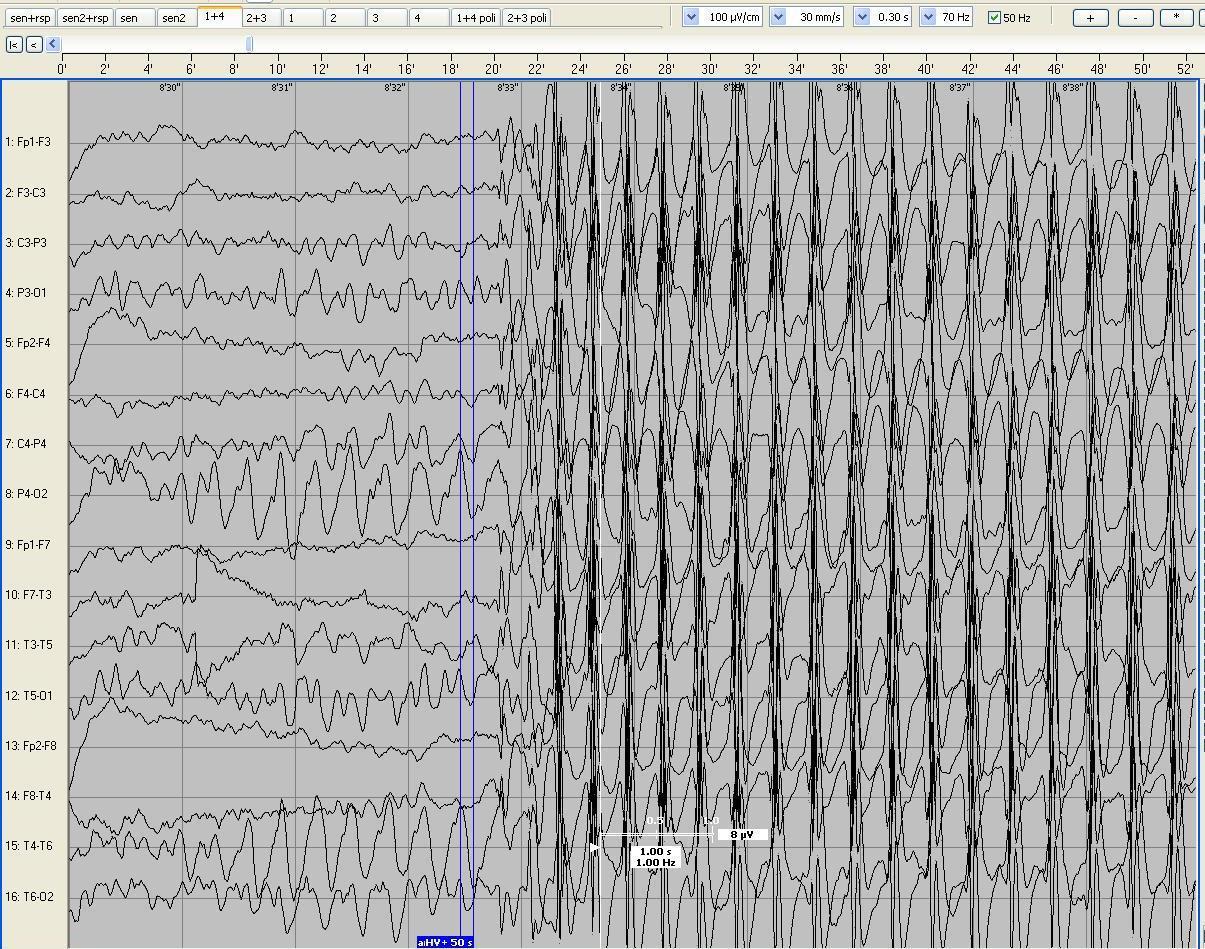

Poniższy zapis czynności bioelektrycznej mózgu został wykonany u 7-letniego dziecka w czuwaniu. W czasie hiperwentylacji (HV) zauważono kilku- sekundowe znieruchomienie dziecka i zarejestrowano wyładowania uogólnione zespołów iglicy z falą wolną o częstotliwości 3 Hz. Całość obrazu (zachowanie dziecka oraz zapis eeg) może odpowiadać: